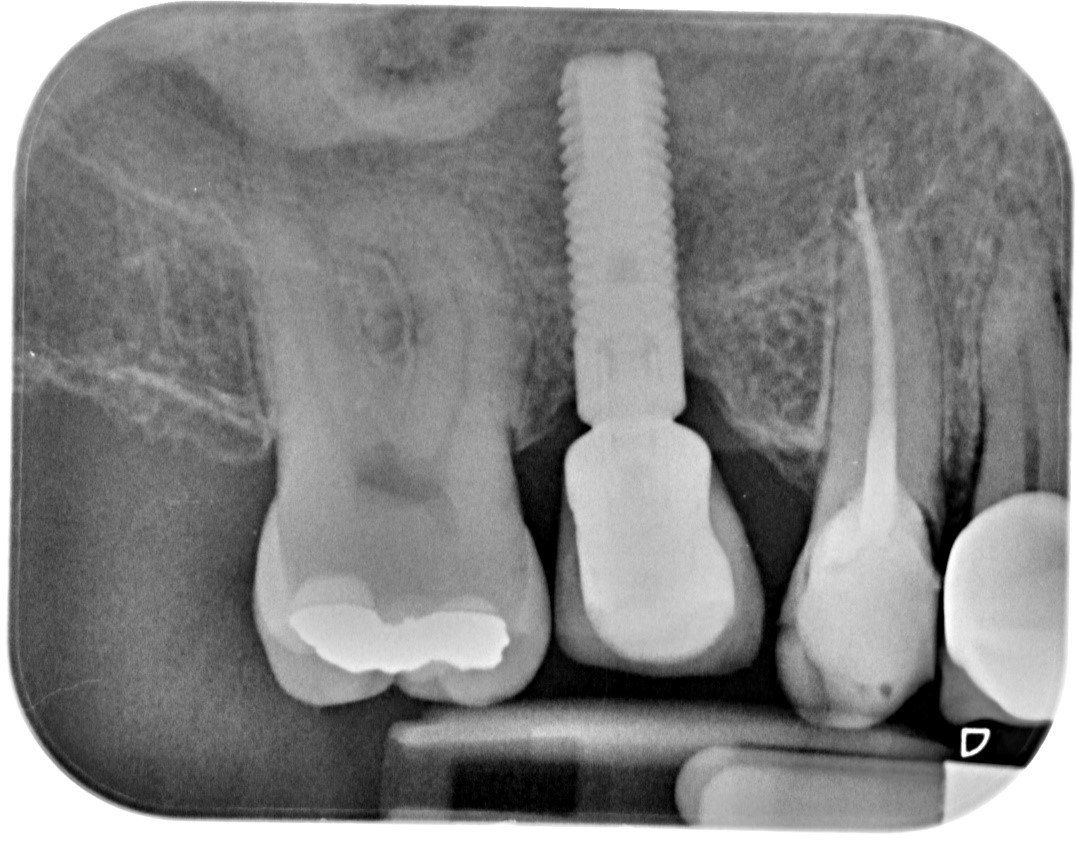

Dopo sei mesi dall’innesto vengono inseriti gli impianti e dopo ulteriori sei mesi vengono applicati i denti in ceramica.

Esiste una seconda modalità chirurgica che consente di ottenere un aumento dei volumi utile all’inserimento degli impianti necessari. Questa tecnica, descritta nel 2003 da Stefan Lundgren direttore del Dipartimento di Chirurgia Maxillo Facciale dell’Università di Umea (Svezia), presenta l’enorme vantaggio di non richiedere nessun innesto di materiale all’interno del seno mascellare sia esso osso autologo del paziente,( il che evita quindi di ricorrere ad un secondo intervento chirurgico di prelievo dal ramo mandibolare) o eterologo vale a dire osso di origine bovina o di natura sintetica che alcuni Autori utilizzano come sostituto dell’osso autologo. Questa tecnica può essere usata in un enorme numero di casi in quanto come vedremo sono sufficienti davvero pochi millimetri (due /tre) di osso residuo per poterla applicare.

Da questo all’idea creare una cavita grazie al sollevamento della membrana sinusale e di inserire degli impianti in essa che stabilizzati in qualche millimetro di supporto di osseo crestale residuo tenevano sollevata la membrana sinusale come il “pilastro di una tenda del circo” il passo fu brevissimo. In questa cavità cosi mantenuta dagli impianti, dopo alcuni mesi, era certa la presenza di nuovo osso attorno ad essi formatosi spontaneamente. L’anno successivo Lundgren definiva la sua tecnica e la consegnava agli operatori di tutto il Mondo.(9)

Circa dieci anni fa il mio gruppo di lavoro ha pubblicato i risultati relativi a quindici pazienti trattati con la tecnica di Lundgren per un totale di 28 impianti seguiti per oltre un anno dopo l’applicazione dei denti. Non fu registrato nessun fallimento. Tutti gli impianti si rivelarono perfettamente integrati dopo un anno di carico e circondati da un notevole volume di osso neoformato. (14)

Un controllo sui medesimi pazienti a distanza di cinque anni ha confermato il mantenimento dell’integrazione ossea in tutti gli impianti, senza nessun fallimento. Al contrario si è rilevato un ulteriore crescita ossea attorno agli impianti. (dati non pubblicati)

Singolo impianto

Cinque anni dopo gli stessi pazienti sono stati nuovamente valutati clinicamente e radiograficamente. Tutti gli impianti risultarono stabili ed asintomatici. La perdita di osso marginale che ad un anno si era rivelata di una media di 0,36mm, dopo cinque anni si è dimostrata essere di 0,7 mm ovvero inferiori ai valori di riassorbimento consentiti di 0,2 mm per ogni anno di carico.